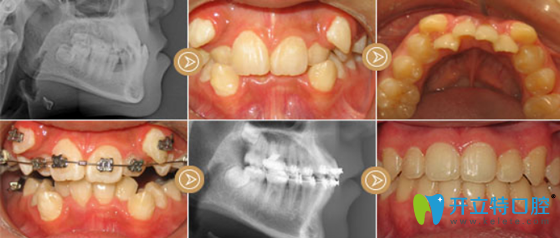

2、虎牙矯正案例

采用技術(shù):金屬鋼絲矯正

好佰年口腔虎牙矯正案例